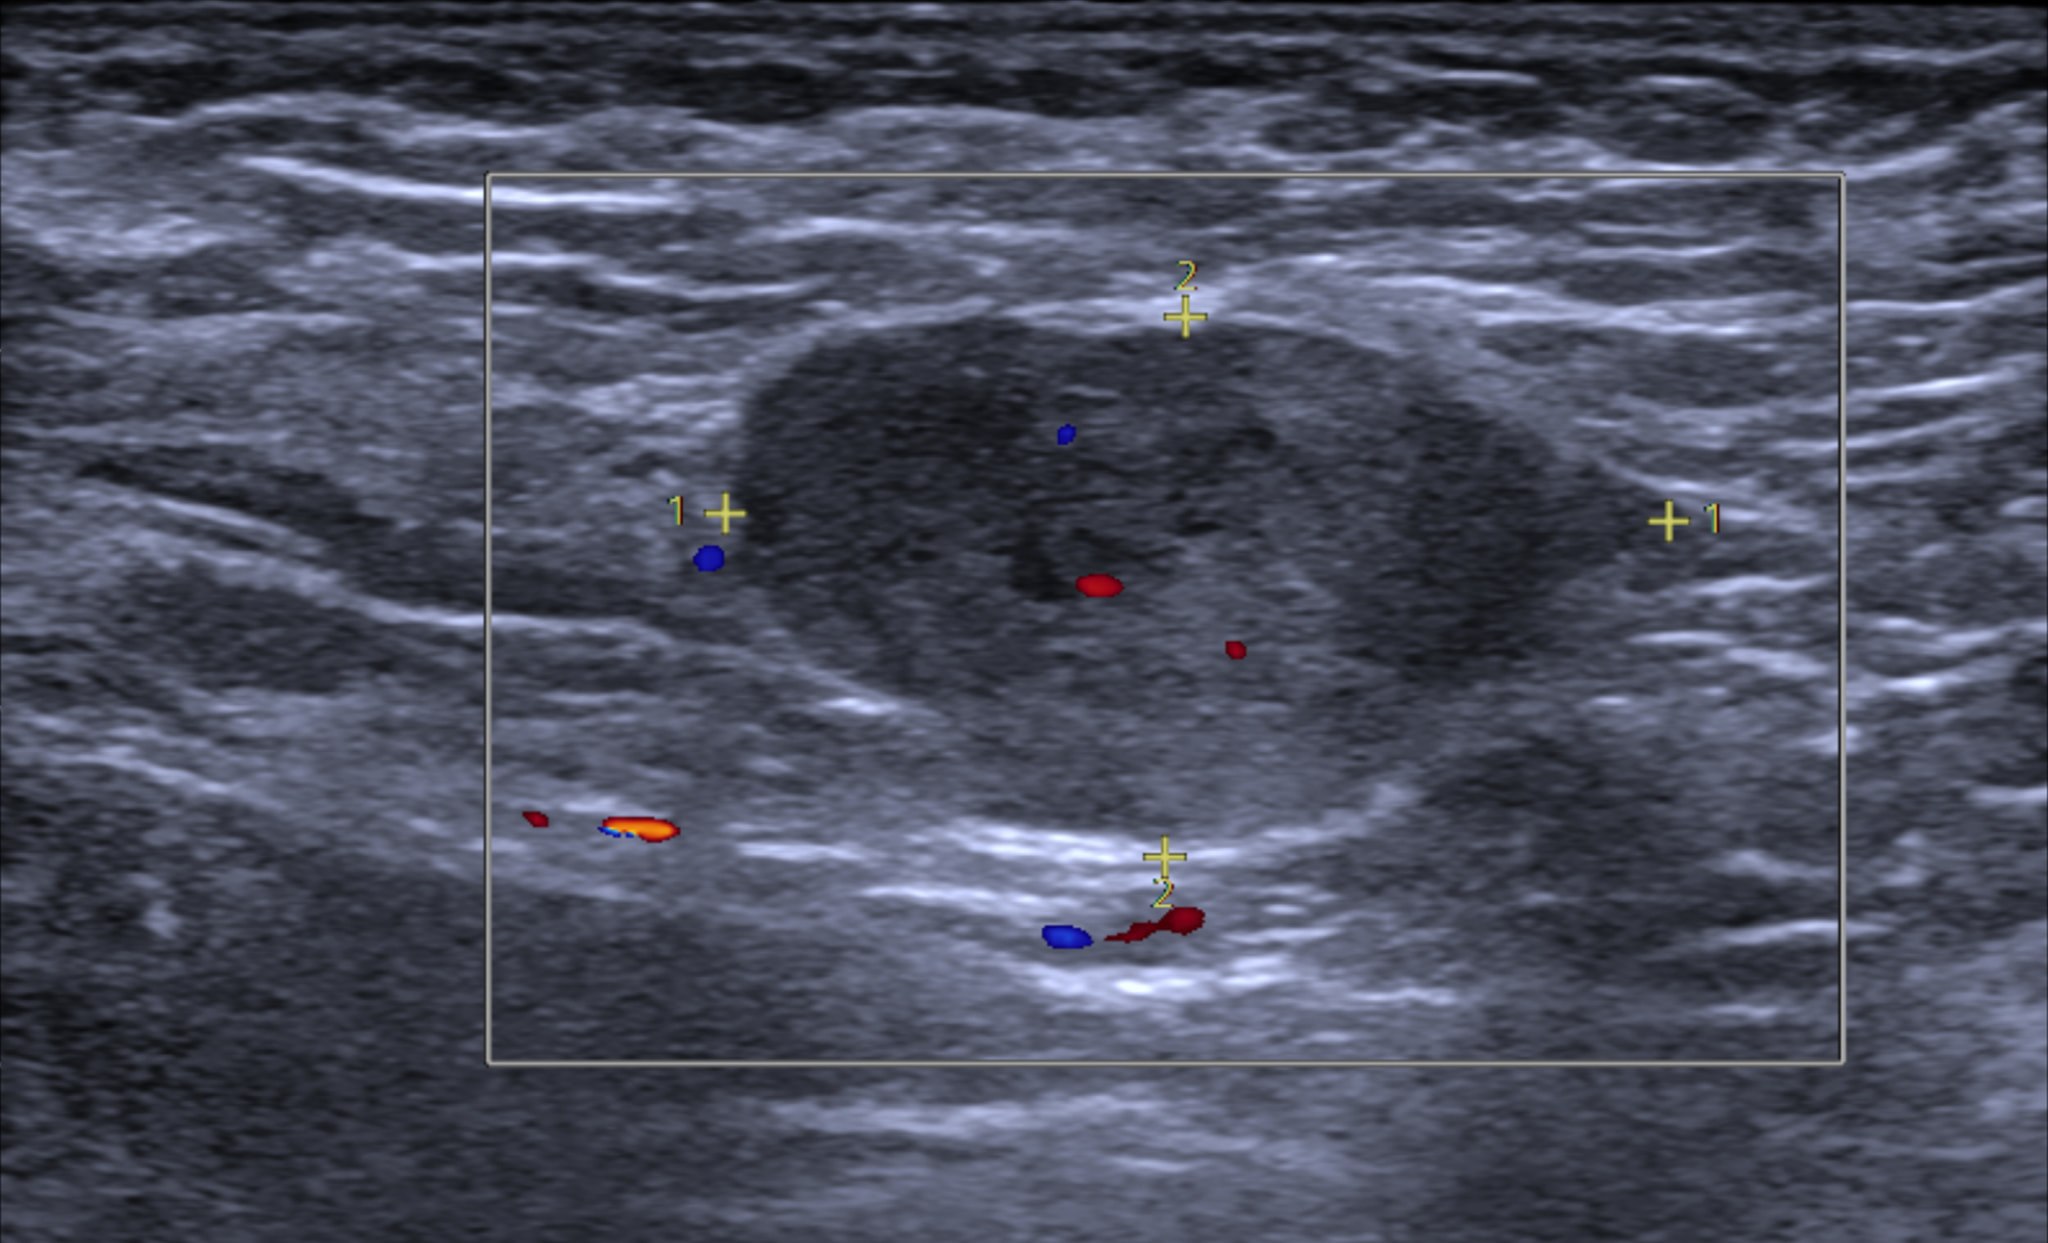

Siêu âm

Siêu âm giúp chúng ta quan sát chi tiết các mô vú và giúp bác sĩ xác định bản chất của khối u vú.